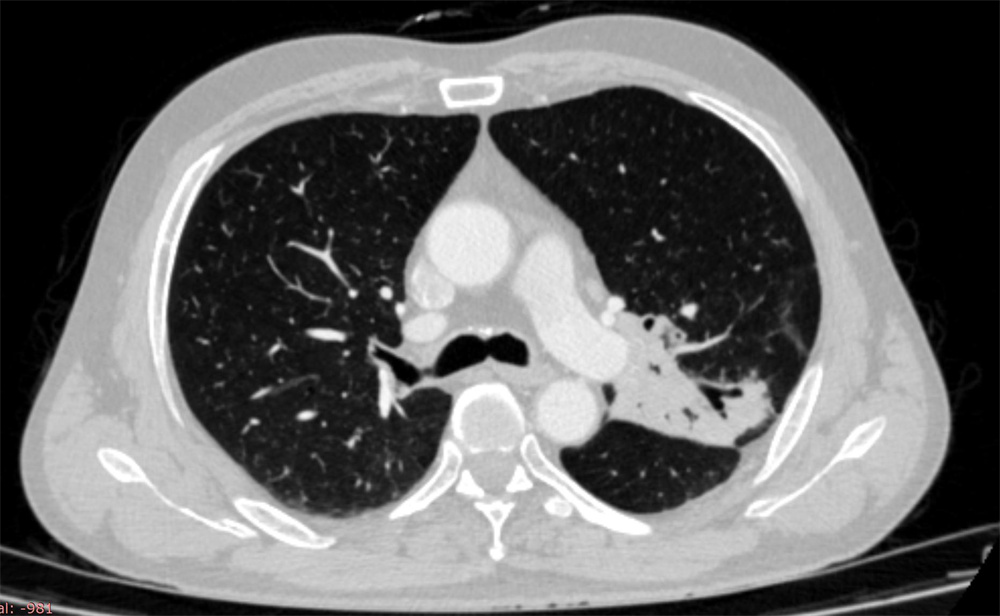

患者王某某因为“间断咳嗽伴胸痛5个月”就诊于我院内一科,入院检查后诊断为“左肺中心型鳞癌(cT3N2M0 ⅢB期)”,且肿瘤侵犯左主支气管及叶间动脉干,手术治疗难以完整切除肿瘤,随即对患者行4个周期的“化疗联合免疫治疗”,复查胸部增强CT示:“左肺上叶肿物,边界不清,呈分叶状,长径约6cm,累及纵隔及叶间裂,纵隔及肺门可见略大淋巴结影。”新辅助治疗效果确切,具备手术指征,随即转入我院胸部肿瘤外二科。

图1 患者术前增强CT图片